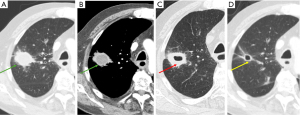

Necrotizing pneumonia and lung abscess

Cavitation within areas of consolidation is a sign of necrotizing pneumonia, often caused by pathogens such as Staphylococcus aureus and Klebsiella pneumoniae. These bacteria are more likely to induce cavitation (Figure 4) (7,8,13). Occasionally, Staphylococcus aureus can occasionally lead to the formation of pneumatoceles, particularly in children (14). Pneumatoceles are thin-walled, cysts that may contain air-fluid levels and typically resolve spontaneously within weeks to a few months (14).

Lung abscesses, a complication of pneumonia, are typically caused by mixed anaerobic infections, with Staphylococcus aureus and Pseudomonas aeruginosa being common culprits (15). Aspiration events are a major risk factor for lung abscesses, with risk factors including alcoholism, poor dental hygiene, impaired consciousness, esophageal motility disorders, and neurological disease (8,15).

In contrast to cavitating pneumonia, which presents with residual consolidation around the cavity, a lung abscess is a more established process, typically showing little to no surrounding consolidation (7). Imaging findings for lung abscesses typically include cavitary lung lesions with or without fluid levels, variable wall thickness (5–15 mm), peripheral contrast enhancement, and a necrotizing center (Figure 5) (7). If the abscess is located peripherally, focal pleural thickening or an empyema may be present (7).